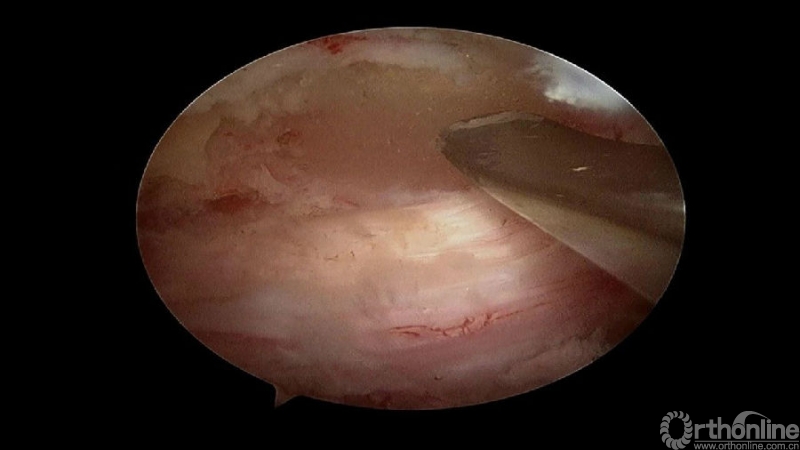

颈椎内镜下单侧入路双侧减压(ULBD)中,减压的难点还是在于识别棘突与椎板的移行部位及对侧结构的显露。

临床上,0°镜子绝对是颈椎UBE的最好用的镜子,但是30°的镜子对侧中线结构的显露及对侧结构的显露具有更广角的视野。在进行同侧减压之前,中线结构的显露是关键。

手术步骤:

1.骨赘位于左侧,选择右侧入路做C4/5椎板切除减压;

2.显露骨赘的内侧面及上下缘;

3.从游离骨块的背侧开始,用磨钻将骨块打薄,然后将骨块的底面与脊髓表面仔细分离,将游离骨块摘除;

4.进一步加深移除骨赘的残余部分,直到显露出对侧的神经根及关节突关节的内壁;

术中操作要点

1. 术中如何确定中线?

2. 术中骨赘的界限?

3. 如何确定对侧结构?

4. 如何确定减压范围?

5. 减压完成后的止血非常重要,高效的止血方法有哪些?

(1)大头等离子刀头止血

(2)小头等离子刀头止血

(3)骨蜡

(4)明胶海绵